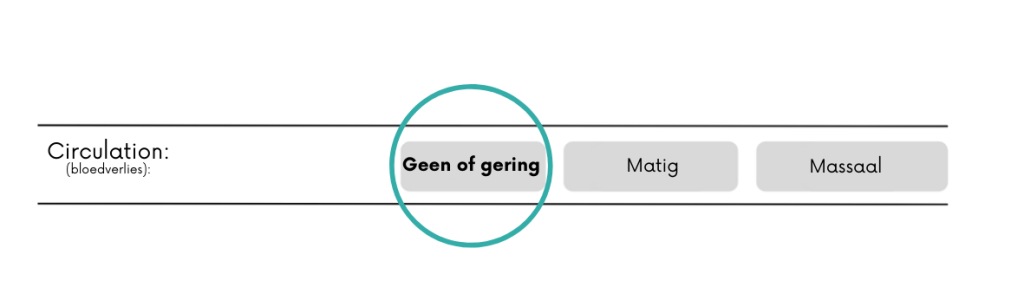

Nee/gering = geen bloeding of beetje sijpelen.

Matig = een bloeding die niet volledig onder controle is te krijgen door het uitoefenen van directe druk.

Massaal = bloed gutst met grote hoeveelheden eruit. Hieronder vallen ook grote hoeveelheden bloed braken of ophoesten.